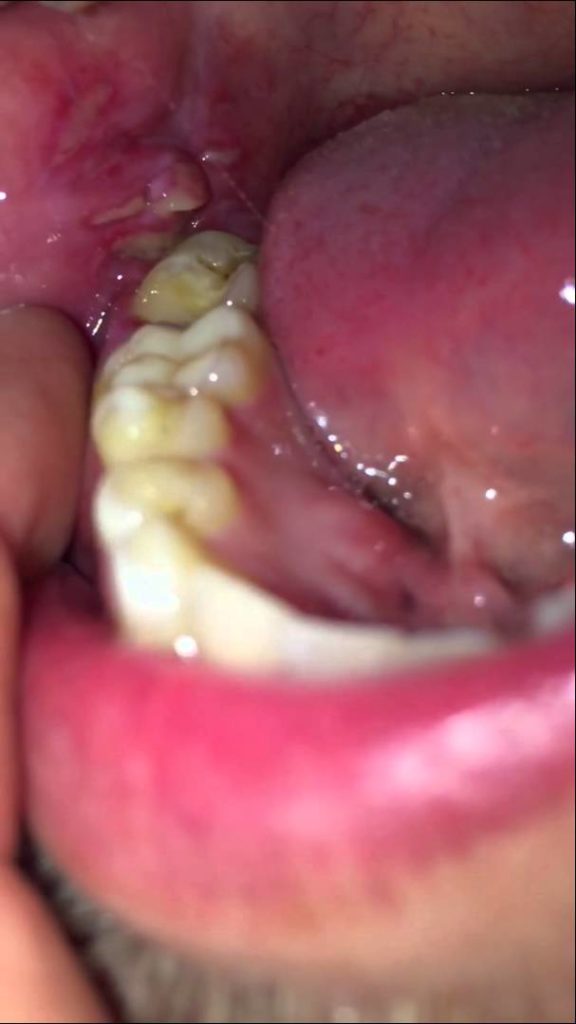

home Health Concerns Infection after wisdom teeth removal Infection after wisdom teeth removal By dentists Posted in Health Concerns Posted on May 4, 2017